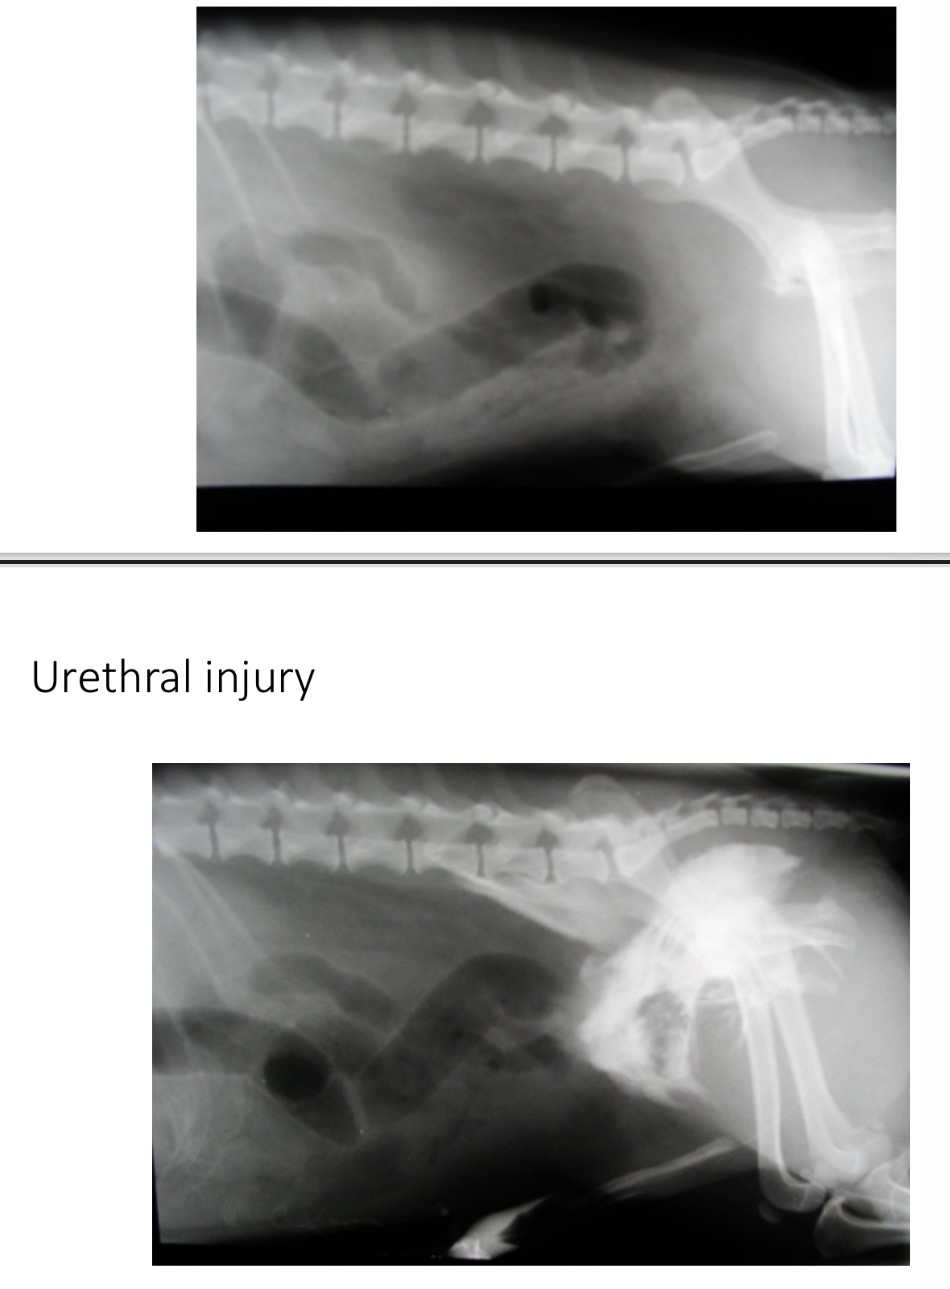

Urethral trauma - causes

Abd Trauma, pelvic fracture, iatrogenic (catheter)

Urethral trauma - CS

Haematuria, dysuria, anuria

Pain

Abd distension

Inappetence, lethargy, V

Collapse

Skin discolouring, cellulitis of perineum+thigh+cd abd

Urethral trauma - Diagnosis

History

Radiography (Plain, retrograde urethrogram)

Serum biochem - inc urea, creatinine, K

Urethral trauma - Treatment

Establish patency with catheter

Stabilise patient

Conservative treatment - in dwelling catheter

Surgery